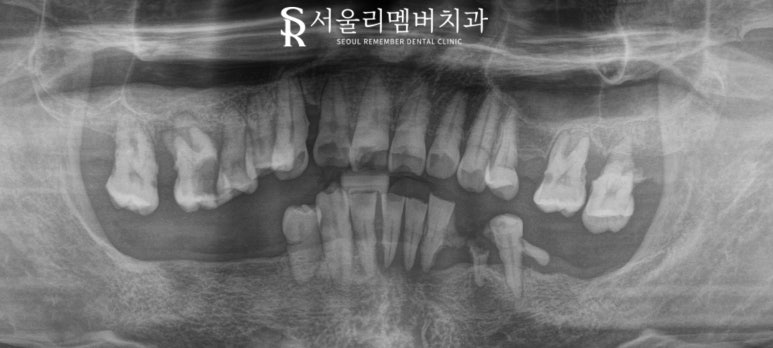

구강 검진

우선 환자의 구강을

살펴볼까요?

환자는 개인 사유로

그동안 구강 위생 관리가

어려운 상태셨습니다.

위턱 전치를 제외하고는

남은 치아들의 모습이

좋지 않아 보이네요.

아랫니의 구치부는

거의 없기 때문에

대합치가 정출되어

수직 고경 또한 무너져 있었습니다.

상악도 잇몸 퇴축으로 인해

이가 흔들리고

뿌리가 다 드러나며

깨진 곳도 많았습니다.

정확한 진단을 위해

파노라마 사진을 본 결과,

상황이 좋지 않은 것을

확인할 수 있었습니다.